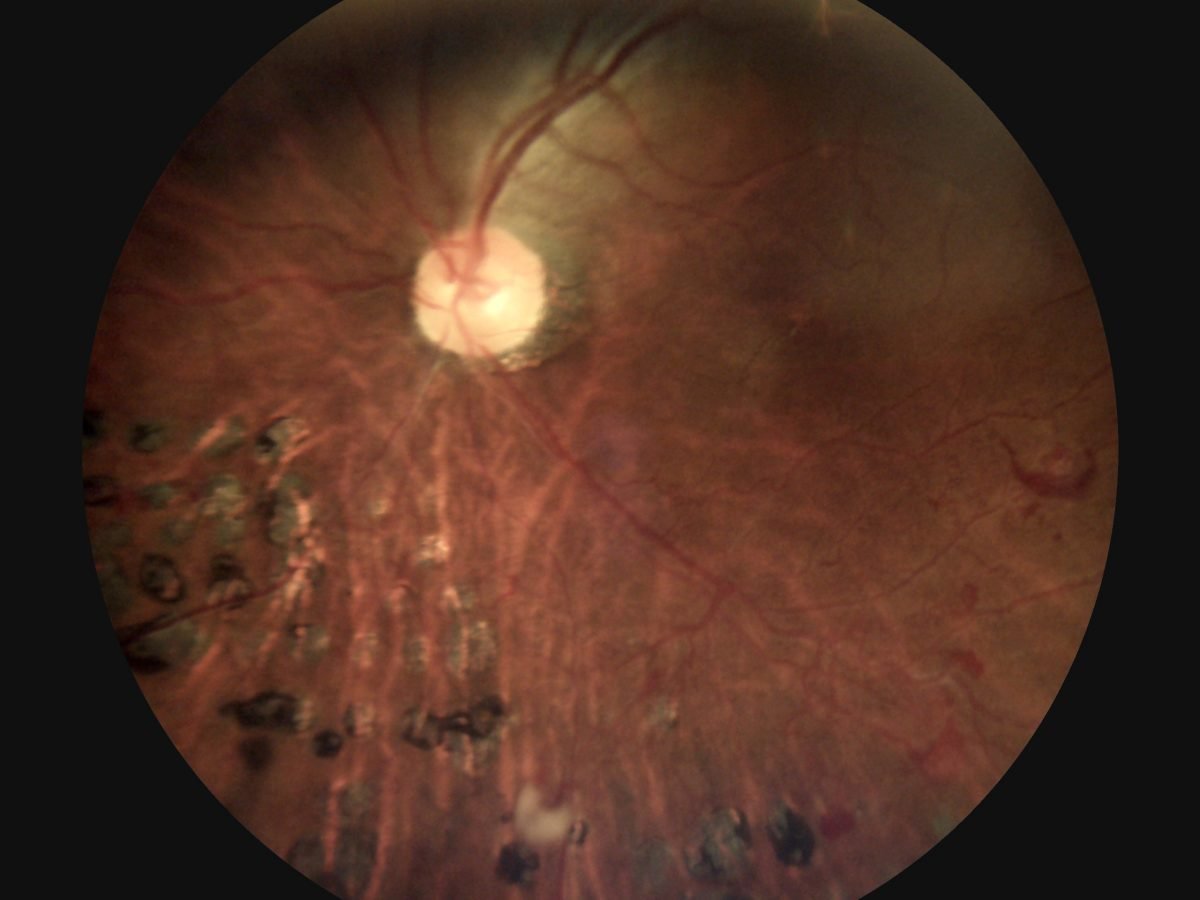

Horus DEC200 Non-Mydriatic Digital Handheld Fundus Camera offers high image quality with ISO 10940 fulfillment.

5MP (2592*1944 pixels) and 45 degree FOV of fundus image are captured to provide more details.

7 internal fixation targets for macula center, disk center and peripheral image in DEC 200 optical modules.

Horus DEC200 provides both auto-focus and power-focus function to facilitate image capturing.